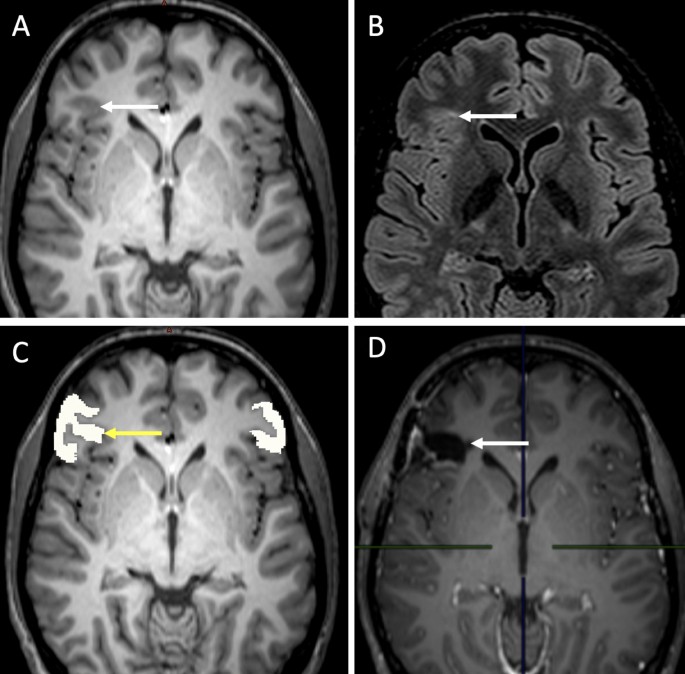

All 28 epileptic patients considered in this study had an increase of the estimated cortical volume confirmed by post-operative tissue analysis. Among these, the average normative values from the LifeSpan model (i.e., the ‘traditional’ approach) identified 11 out of 28 patients with increase of estimated cortical volume, while our generative manifold learning analysis GeoNorm identified 17 out of 28 patients with increase of estimated cortical volume based on the personalized normative values (a further 55% more subjects detected). Figure 1 shows an example of a patient with confirmed FCDII. In this patient, AssemblyNet 1 estimated the inferior triangular gyrus occupies 0.35% of the total ICV. The LifeSpan average normative range for this part of the cortex was [Inferior: 0.21 Superior: 0.39]%, therefore considered normal. In contrast, the personalized normative values from GeoNorm found the following normative range: [0.21; 0.34]%, therefore classifying the right inferior triangular gyrus as abnormally increased.

Example of a 18-year old patient with surgically confirmed FCDII of the right inferior triangular gyrus; MRI was considered abnormal by the senior radiologist. (A) Presurgical T1-weighted imaging: the white arrow shows focal thickening of the cerebral cortex at the level of the right inferior triangular gyrus. (B) Presurgical FLAIR sequence: the white arrow shows a subcortical region with FLAIR signal hyperintensity at the level of the dysplastic zone. (C) AssemblyNet segmentation of the right inferior triangular gyri, the yellow arrow shows the right sided region. (D) Postsurgical T1-weighted scan: postoperative cavity (white arrow).

The sensitivity of the personalized normative values on the resected zone was 0.67 (i.e. 17 patients out of 28 with cortical hypertrophy on MRI further confirmed by surgery) while that of the average normative values was 0.39 (i.e. 11 patients out of 28). Note that 0.67 was also the sensitivity of the radiological report (i.e. 17 patients out of 28, see Table 1).